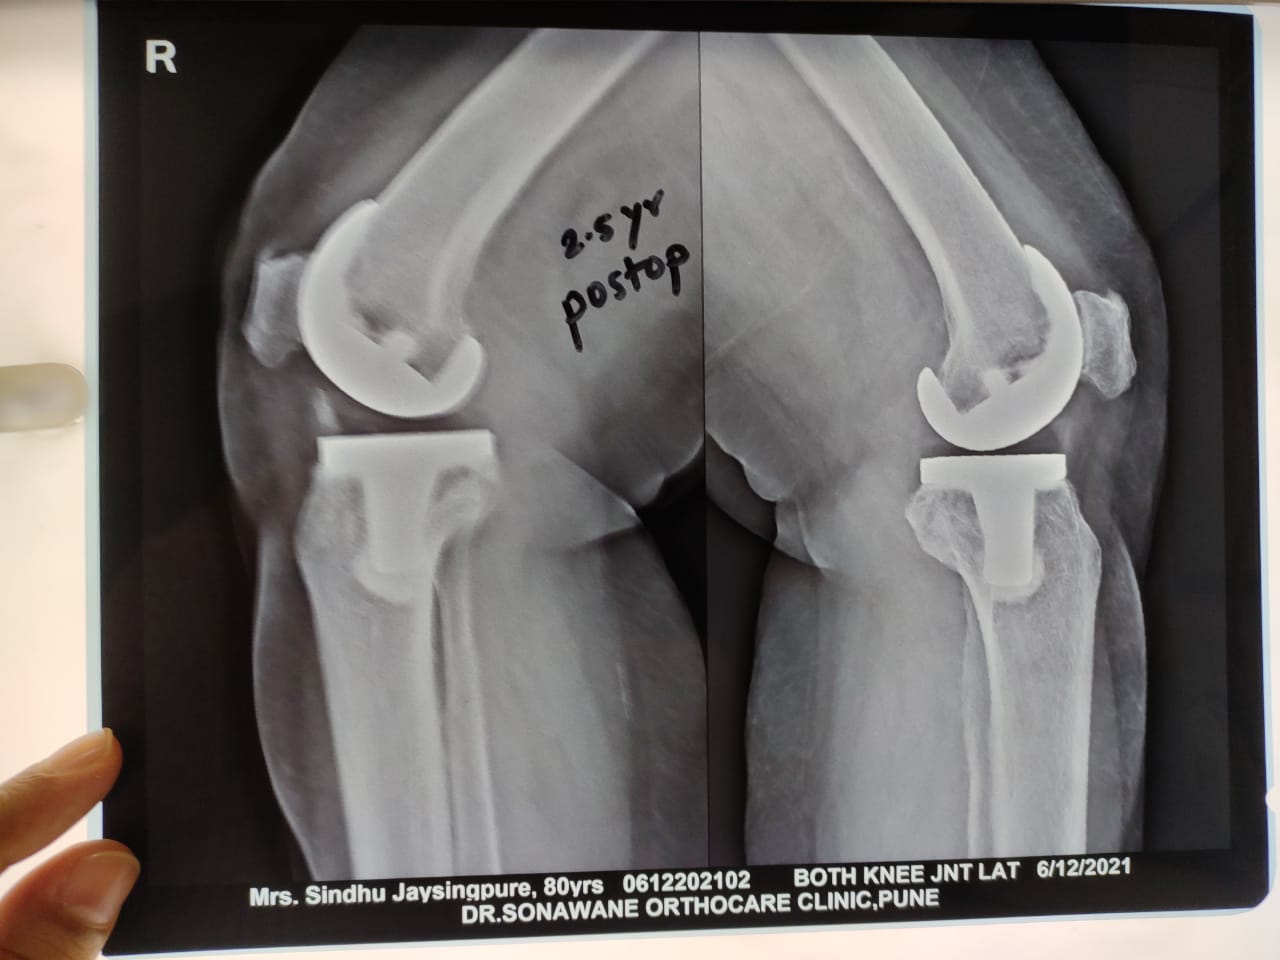

Dr. Sonawane Orthocare clinic is a centrally located Orthopedic Clinic In Pune city near Swargate at Hirabaug Business Centre, Hirabaug chowk, Tilak Road, Shukrawar peth and has easy accessibility from all parts of the city with multiple modes of travelling and enough parking spaces for patients’ own vehicles. Clinic is very modern and stylish and has air conditioned waiting area with comfortable sitting arrangement along with other amenities like TV, Wi-Fi, newspapers. There is hassle-free appointment and consultation system which is totally computerized. Patients get system generated appointment messages, reminders for follow-up dates and prescriptions through messages and emails. So its easy to keep track, keep and carry records and access it anywhere in the world. Clinic offers in-house digital X-ray, pathology tests and physiotherapy facilities at very reasonable rates. This makes the clinic a one stop destination for the patients they don’t need to go anywhere else for these facilities, saving lots of time and effort to get the treatment. We at Dr. Sonawane Orthocare clinic are committed for the best orthopedics care and proud to be one of the best orthopedics clinics in Pune.